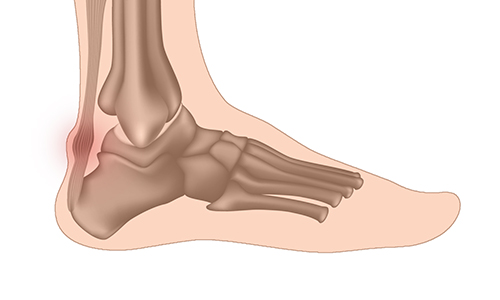

Douleur au talon qu est ce qui peut en etre la cause PodFormance